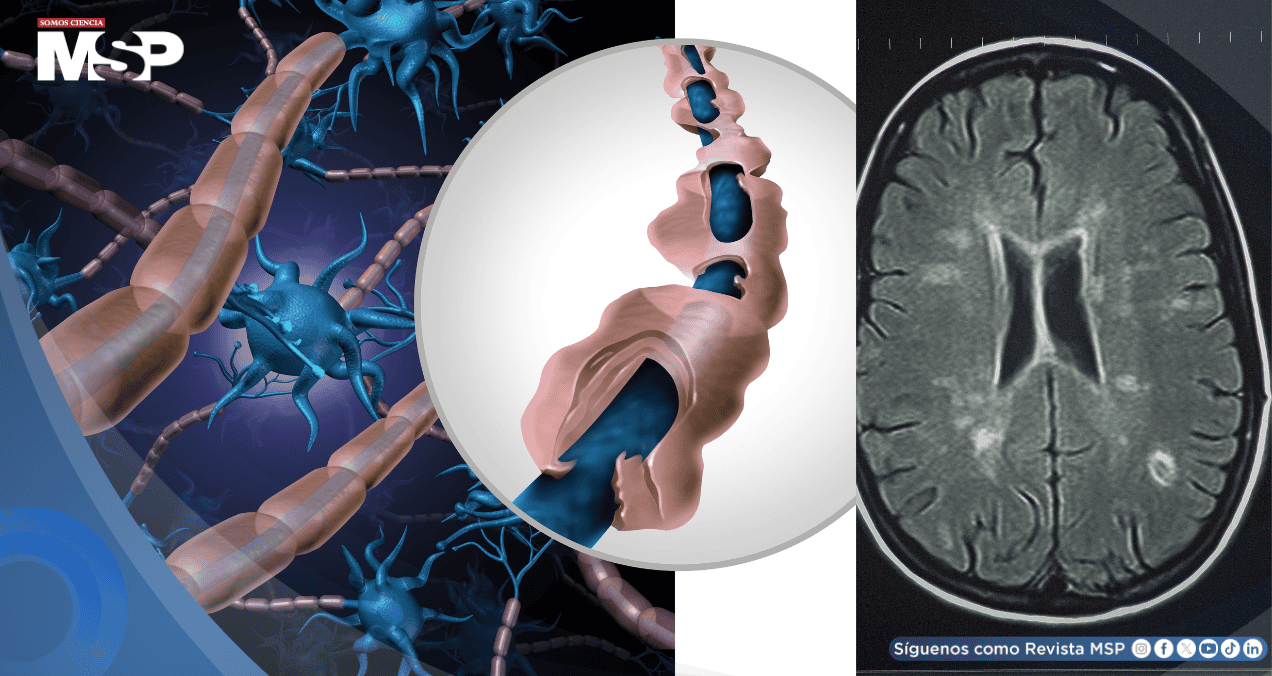

El RIS corresponde a hallazgos radiológicos incidentales —lesiones cerebrales compatibles con EM— que se detectan en personas que se someten a una resonancia magnética por motivos no relacionados con síntomas neurológicos.

Uno de los hallazgos clave fue la asociación entre niveles elevados en sangre de neurolamentos de cadena ligera (sNfL) —proteínas intracelulares que se liberan en casos de daño neuronal— y el riesgo de aparición de síntomas.